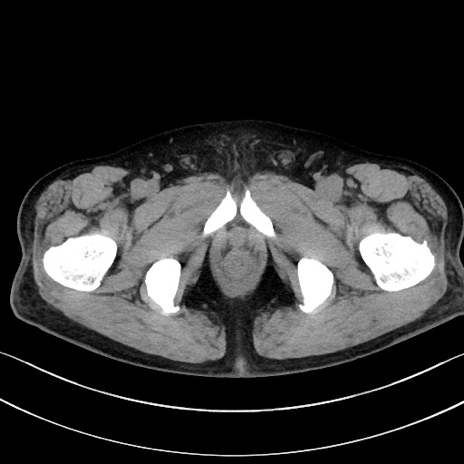

症例15(横断像)

【症例】70歳代男性

【主訴】腹痛

【現病歴】今朝から腹痛あり。全体的に痛い。特に左上の方。排ガスが今日はない。冷や汗が出る。

【既往歴】直腸癌術後

【身体所見】左側腹部〜上腹部に圧痛あり。腹膜刺激症状明らかなではない。軽度反跳痛。左下腹部に術後瘢痕あり。

【データ】WBC 7700、CRP 0.02